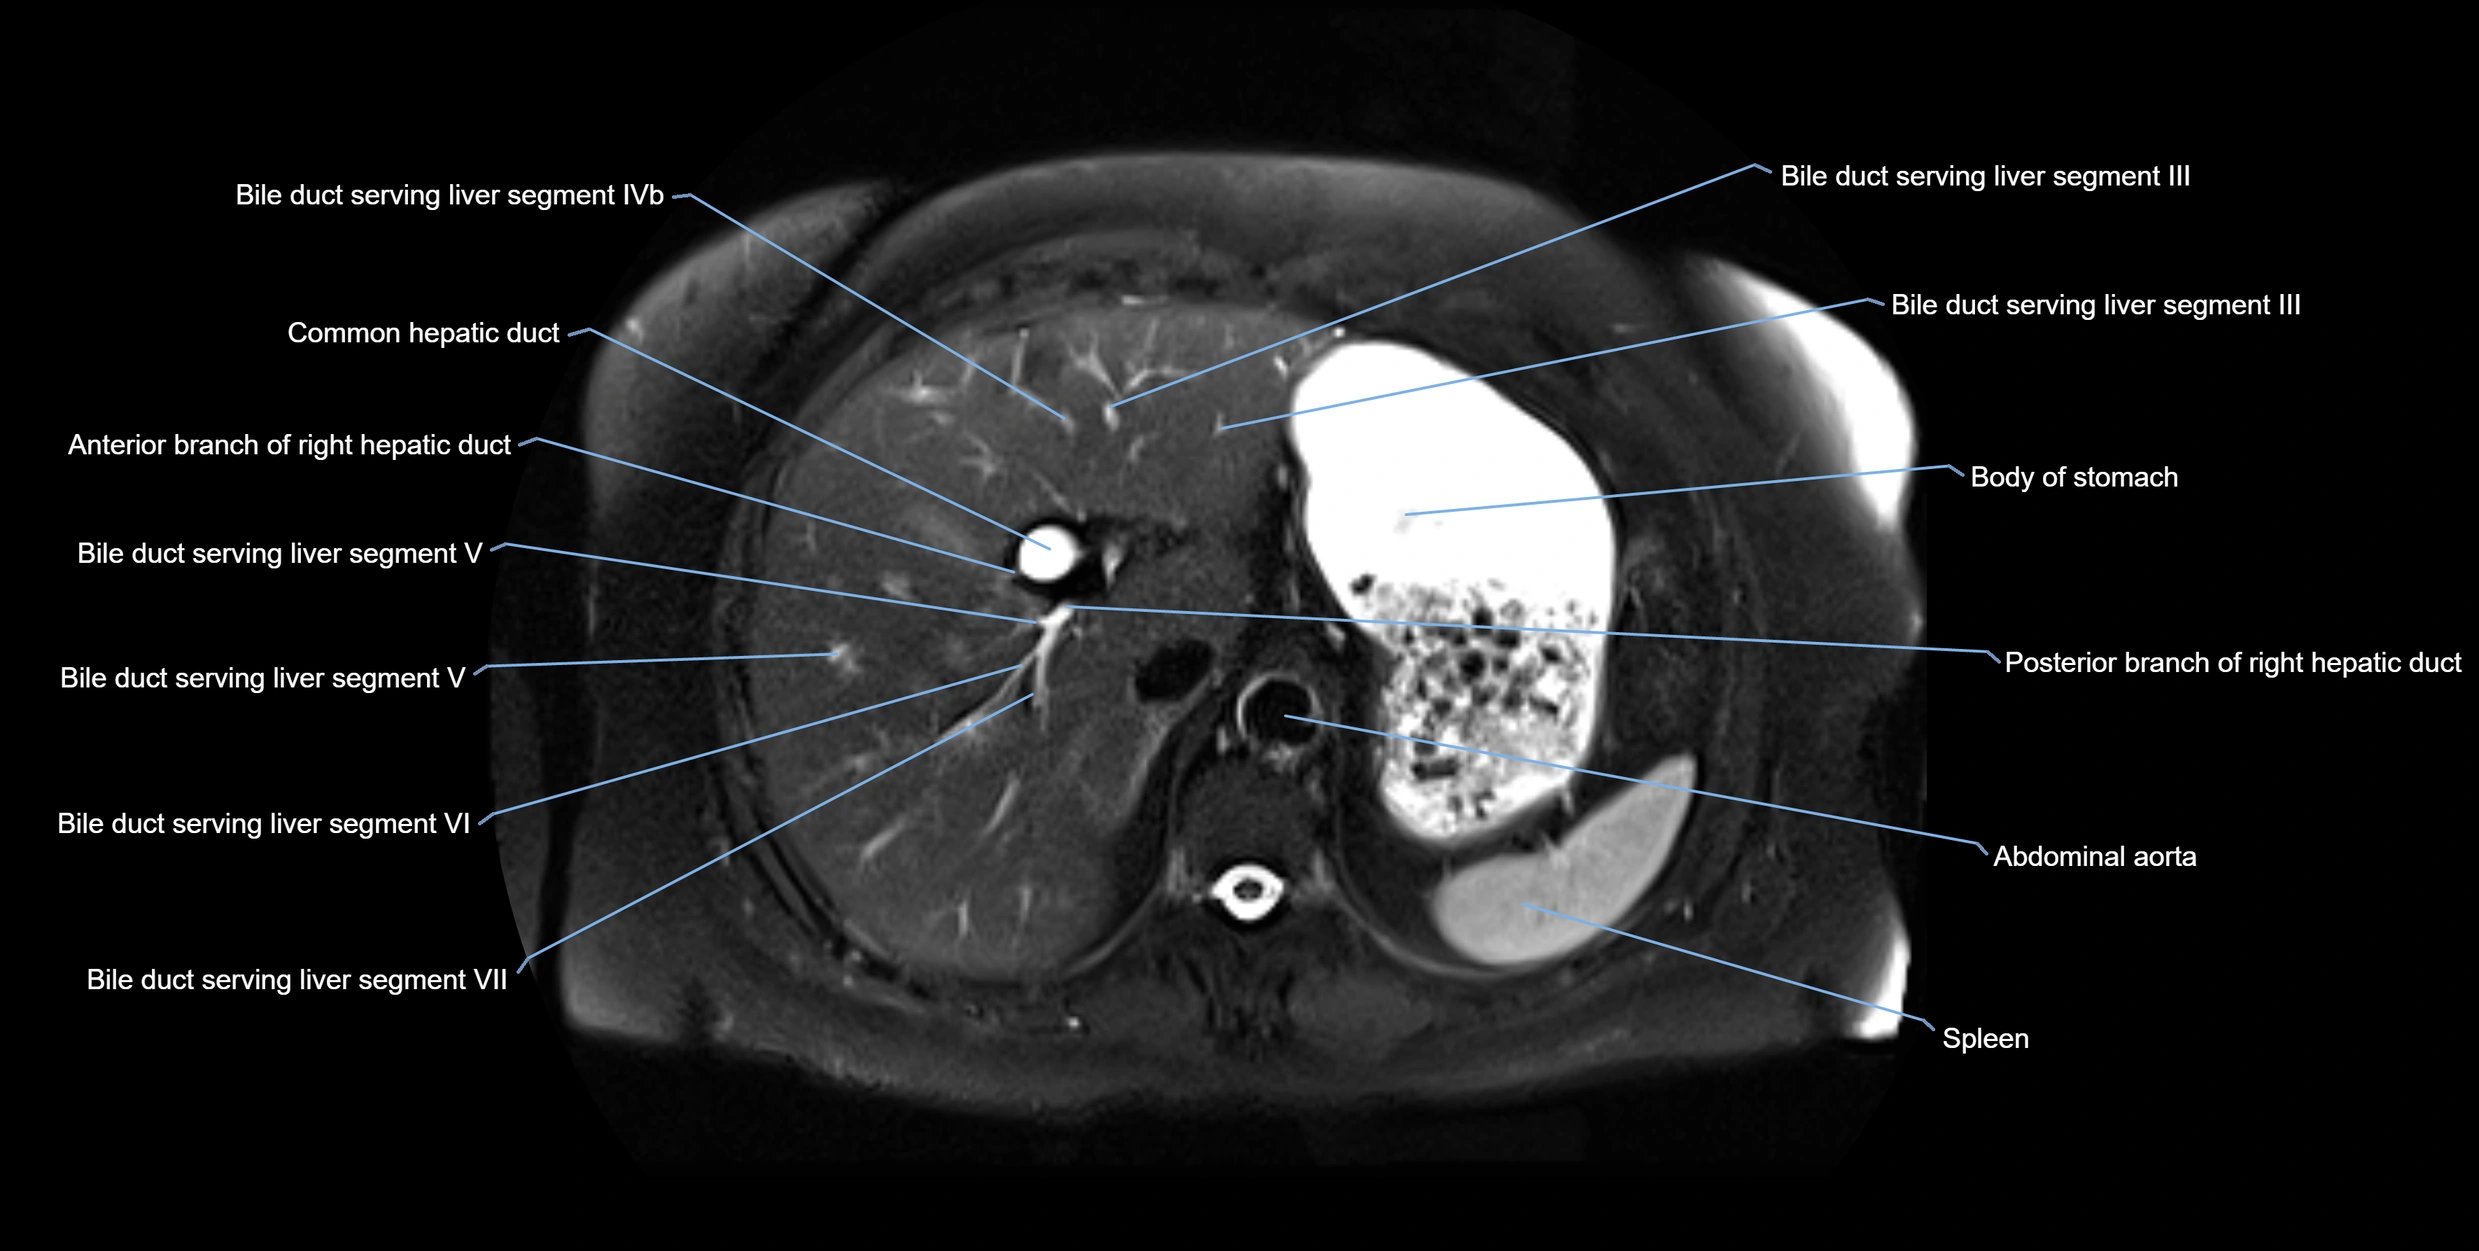

T2-weighted images:

• Duct fluid appears bright

• Accessory duct seen as a fine high-signal tubular structure in pancreatic head

T2 Fat-Saturated HASTE (single-shot):

• Accessory duct: bright, thin linear structure in pancreatic head

• Stones, strictures, or air bubbles appear as dark filling defects

• Excellent for rapid evaluation of duct patency

MRI image

image